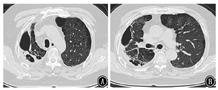

患者男,64岁,因"反复咳嗽、咳痰、喘憋18年,加重20余天"于2018年1月26日入院。患者近18年反复出现咳嗽、咳痰、喘憋,诊断为COPD、肺气肿、肺大疱、矽肺Ⅰ期等。近3年因COPD急性加重多次住院,经抗感染、化痰、平喘等治疗可好转,院外长期吸入沙美特罗替卡松粉(舒利迭)、噻托溴铵粉(思力华),口服止咳、化痰药物。2018年1月3日患者受凉后再次出现咳嗽、咳痰、喘憋加重,就诊于北京某医院。2018年1月3日胸部CT示两肺见多发粗大索条影,边缘模糊,肺气肿,多发肺大疱,左肺下叶球形肺不张,双侧胸膜肥厚,右侧胸膜钙化,右肺下叶支气管扩张(图1),考虑肺部感染。住院后给予哌拉西林舒巴坦钠、比阿培南、莫西沙星等抗感染,并给予甲泼尼龙抗炎(具体不详)。患者病情好转,于2018年1月24日出院。出院后按医嘱继续口服醋酸泼尼松40 mg/d。2018年1月26日患者出现发热,体温最高达38 ℃,咳嗽、咳痰、憋喘较前加重,安静状态憋喘,咳痰带鲜红血丝,伴纳差、乏力,无盗汗,无胸痛,无头晕、恶心,来北京老年医院急诊就诊。血常规:白细胞计数23.69×109/L,红细胞计数5.42×1012/L,血红蛋白158 g/L,血小板计数173×109/L,中性粒细胞比例87.3%,淋巴细胞比例5.7%;血气分析:pH值7.45,PaCO2为41.4 mmHg(1 mmHg=0.133 kPa),PaO2为72.2 mmHg,SaO2为94.5%;血凝指标、D-二聚体、肌钙蛋白I、肌酸激酶同功酶、B型钠酸肽均正常。2018年1月26日胸部CT与2018年1月3日比较,双肺新出现散在斑片影及斑点影,伴大小不等空洞,部分空洞周围可见晕征(图2),考虑双肺感染进展,收住北京老年医院呼吸康复科。